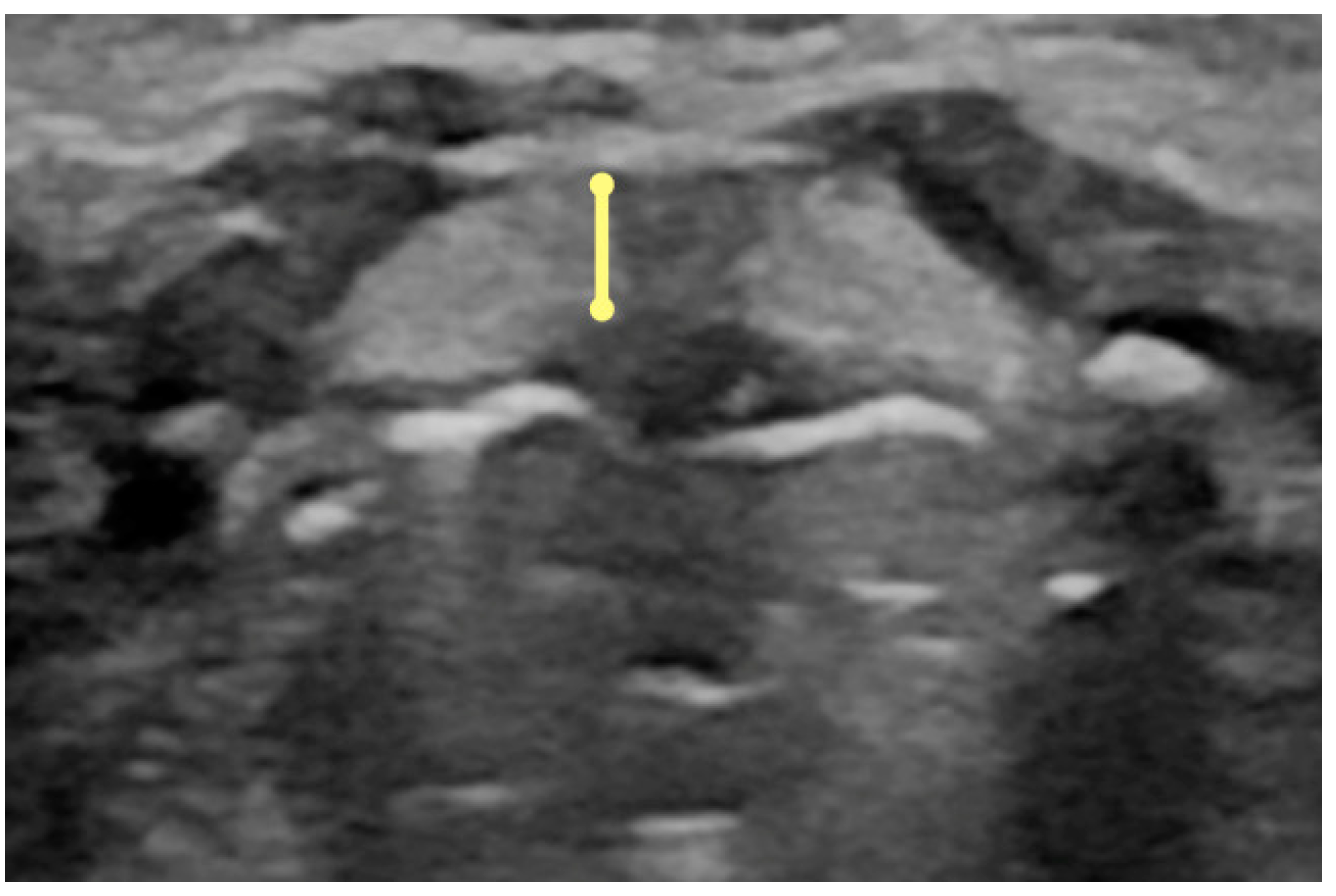

- Thickness of the infrahyoid muscles at the level of the thyroid cartilage and hyoid bone (measurement taken in the transverse view of the thickest dimension between the outer edges of thyrohyoid and sternohyoid muscles as a group of infrahyoid muscles in the transverse plane, at the level of well-visible hyoid bone and glottis) (Figure A14).